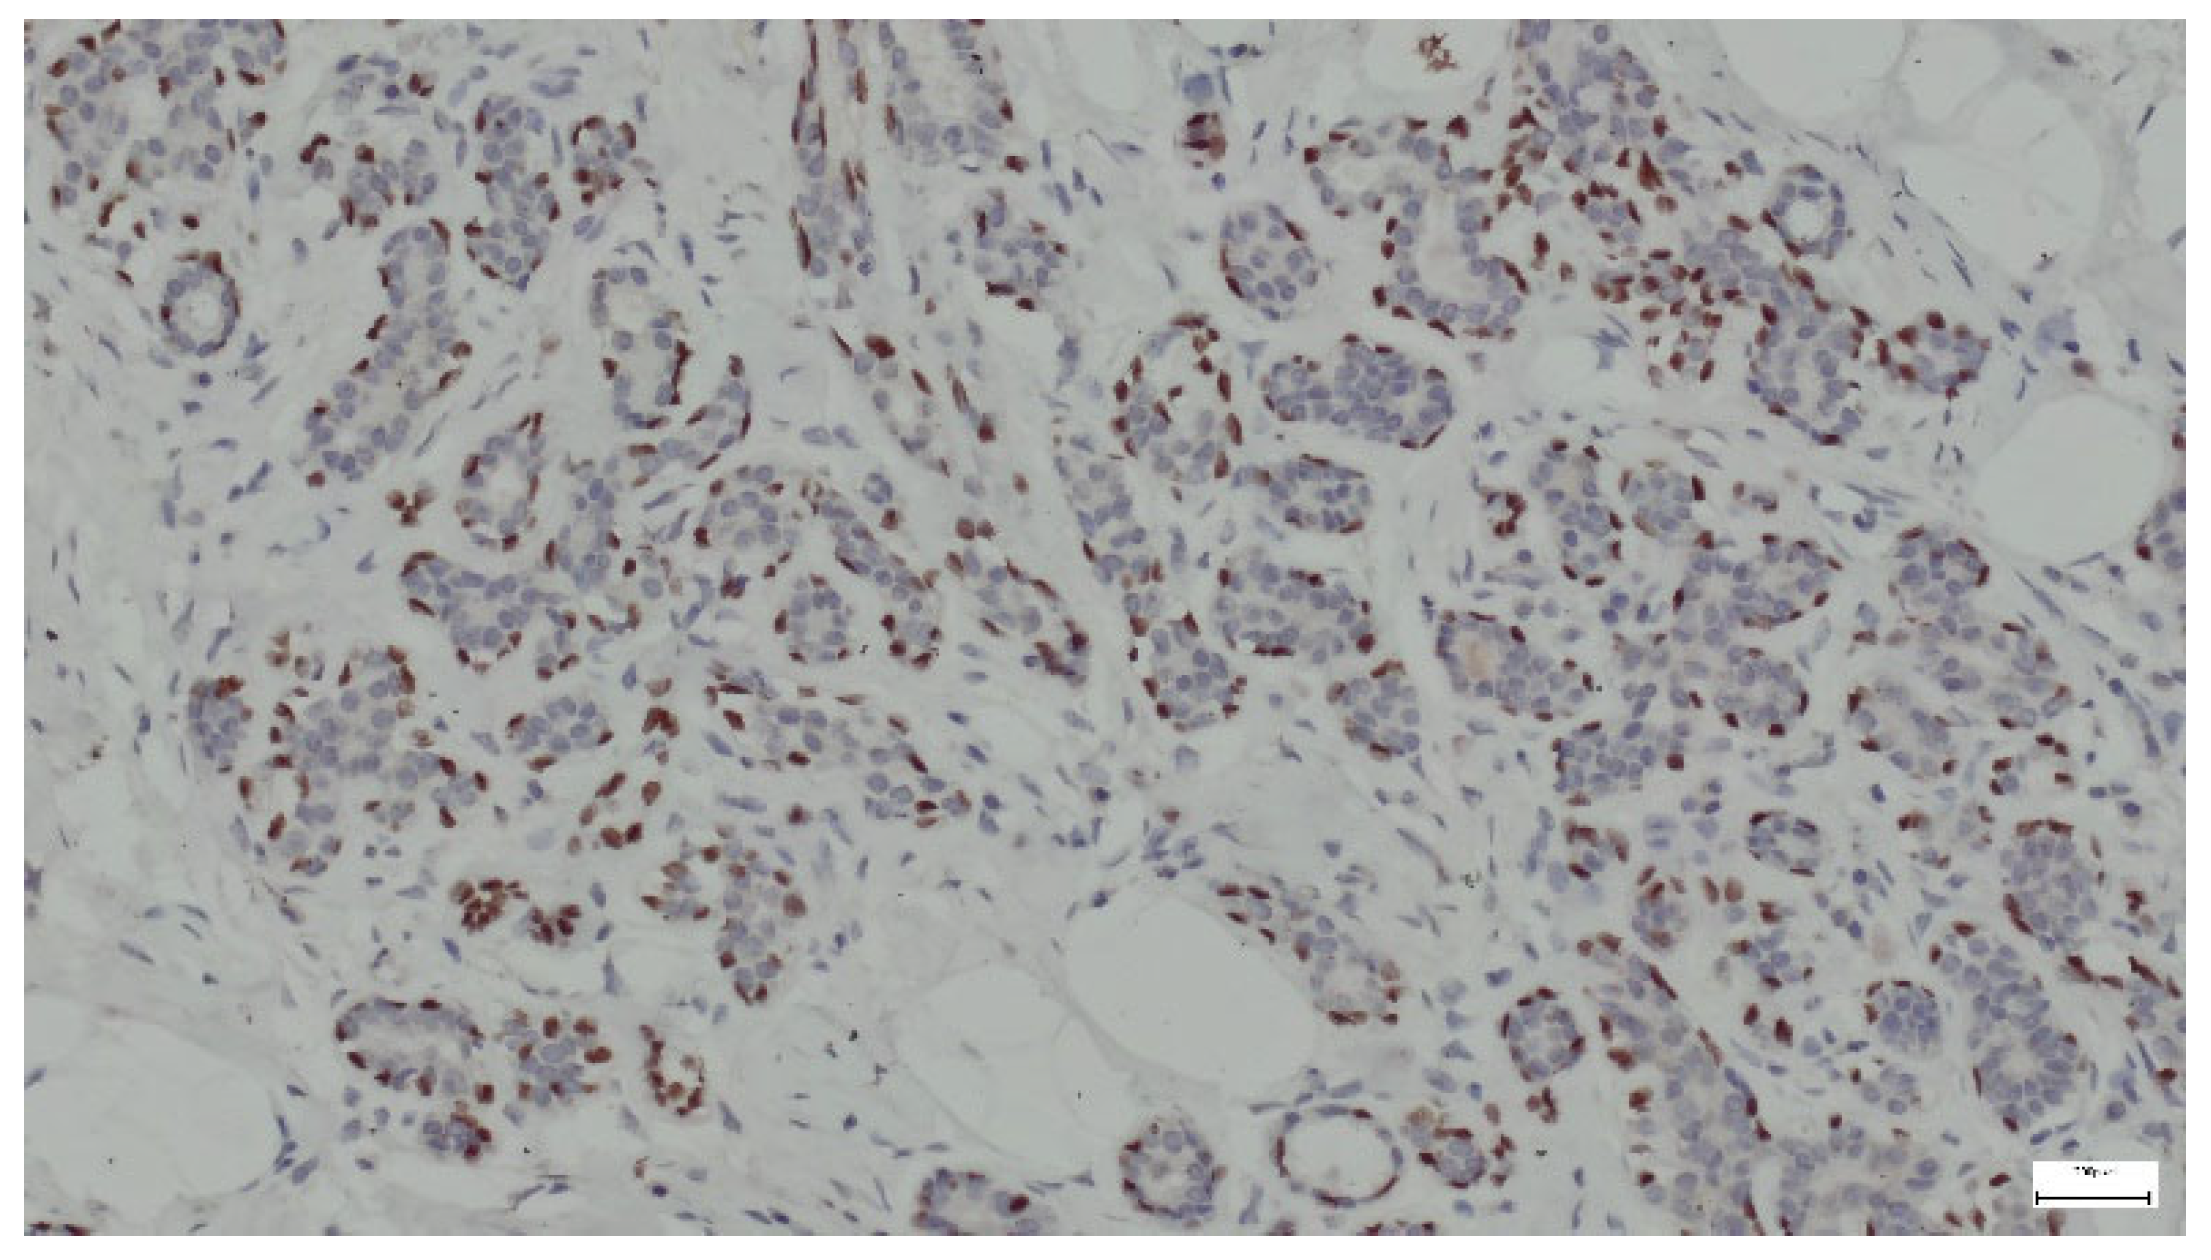

p63 is a protein that serves as a marker for basal cells in various tissues, including the breast. In the context of breast hamartoma, p63 expression can help differentiate between benign and malignant lesions and may provide insights into the myoepithelial cell population within the tumor. In all cases, p63 was strongly expressed in the nuclei of myoepithelial cells surrounding the ducts and lobules (Figure 15).

Figure 15.

p63 expression in ducts and lobules lined by epithelial and myoepithelial cells (anti-p63 ×10).

In addition to histological evaluation, breast hamartoma can be confirmed by IHC, where glandular components that contain normal breast ducts and lobules are highlighted by ER, SMA, and p63. Immunostaining aids in the differentiation of breast hamartomas from malignant lesions and contributes to a detailed characterization of these benign entities. ER expression in breast hamartomas can indicate hormone responsiveness, similar to other benign and malignant breast lesions. ER can also be expressed in the stromal component of the hamartoma, though this is less common. Smooth muscle actin (SMA) staining in breast hamartomas can help identify the presence and distribution of myoepithelial cells around glandular structures. SMA can also stain myofibroblasts in the fibrous stroma of breast hamartomas. The staining can highlight pericytes and smooth muscle cells in the walls of blood vessels within the hamartoma [40]. p63 is a member of the p53 family of transcription factors and is involved in the development and maintenance of epithelial tissues. It is commonly used as a marker for myoepithelial cells in the breast and other tissues. The detection of a continuous layer of p63-positive myoepithelial cells around ducts and lobules supports the diagnosis of a benign lesion [40].